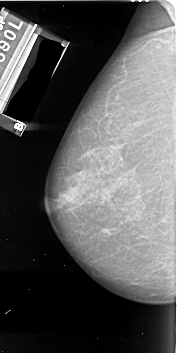

A_1007_1.LEFT_MLO

LEFT_MLO LINES 4801 PIXELS_PER_LINE 2521 BITS_PER_PIXEL 16 RESOLUTION 42 NON_OVERLAY